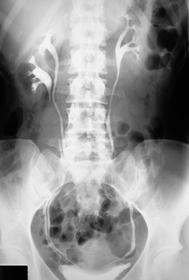

Hydronephrosis Water in the nephrons of the kidney (there is no actual water though) Results from an obstruction of the renal pelvis, calyces, and ureter due to back pressure of urine that can't flow pas the obstruction Is NOT an actual disease but results from another Occurs bilaterally in pregnancy due to fetus pushing against ureters Symptoms: hematuria, pyuria, flank pain, fever Radiographic Appearance: IVU-enlargement above the obstruction and no anatomy demonstrated below, calyces are sharp in appearance with enlargement